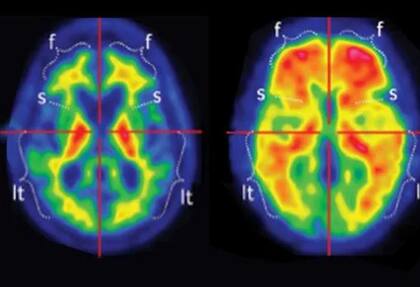

Para llevar a cabo el estudio, los investigadores evaluaron a 76 voluntarios mediante electroencefalogramas (EEG) mientras participaban en un juego de aprendizaje basado en recompensas. Durante la prueba se utilizaron alimentos como: 1) dulces, 2) chocolate, 3) papas fritas y 4) pochoclo.

No obstante, los registros eléctricos mostraron que las áreas cerebrales vinculadas con la recompensa mantenían una respuesta similar ante las imágenes del alimento, incluso después de que los participantes estuvieran completamente saciados.